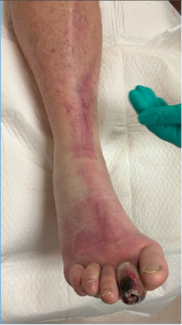

Vibrio vulnificus necrotizing fasciitis is a rapidly progressive, often fatal soft tissue infection that demands immediate clinical recognition and decisive surgical management. This case underscores the limitations of relying on the LRINEC...